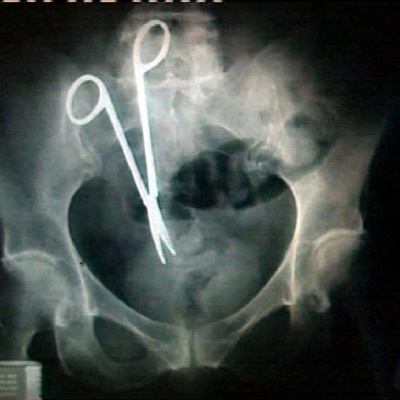

Jedes Jahr erstellt der Medizinische Dienst des Bundes etwa 13.000 Gutachten zu vermuteten Behandlungsfehlern. In etwa einem Viertel der Fälle bestätigen die Gutachten einen solchen vermeidbaren Fehler.